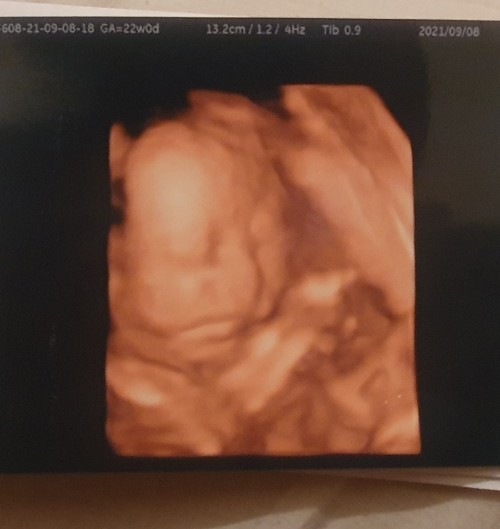

กำหนดคลอด 17 ธ.ค.64 นน.แม่ขึ้นมา 5 กก. นน.ลูก 1 กก. ซาวน์ตอน 26 วีค 😊

บ้านนี้19ธันวา64 ท้องแรก เบบี๋ นน.1,219g 28w6d#ธีมลูกสาว👼🧸❤️🌈